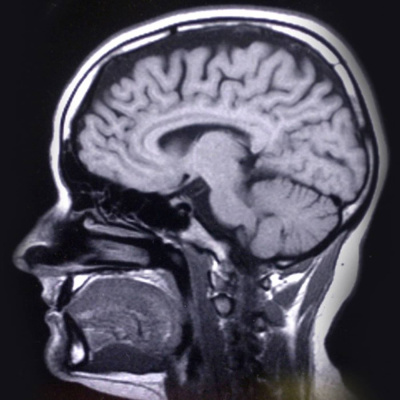

Lars Nyberg är hjärnforskare fråga vad du vill! Han vet allt om hur ditt minne funkar. Vad händer med minnet när du blir äldre? Skiljer sig våra hjärnor från varandra? Programledare Hanna Palm. Lyssna på alla avsnitt i Sveriges Radio Play.